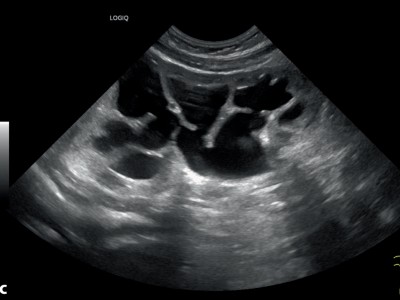

Gas, E. coli, Diabetes – in diesem Notfall sind Sie gefragt

Ein unkontrollierter Diabetes mellitus besteht bei bis zu 95 % der Patienten mit emphysematöse Pyelonephritis. So auch bei dem 55-jährigen Patienten, der notärztlich mit dem Leitbild eines akuten Abdomens vorgestellt wird. Die Diagnose ist nur radiologisch möglich. Ursächlicher Erreger in diesem Fall ist E. coli. Wissen Sie, wie therapiert wird?

Arzt reicht Patientin Urinbecher/© terovesalainen / stock.adobe.com (Symbolbild mit Fotomodellen), Urintest/© AlexRaths / Getty Images / iStock, Person hält sich den Bauch/© anut21ng Stock / stock.adobe.com (Symbolbild mit Fotomodell), Laborkraft benetzt einen Urinteststreifen/© Lothar Drechsel / Stock.adobe.com (Symbolbild mit Fotomodell), Injektion in einen venösen Zugang/© sudok1 / Getty Images / iStock, Arzt tastet Bauch eines Mannes ab/© Kate / Stock.adobe.com (Symbolbild mit Fotomodell), Senior hält Tabletten und Glas Wasser in den Händen/© Andrii Zastrozhnov / Stock.adobe.com (Symbolbild mit Fotomodell), Teststreifen zur Urin-Analyse/© Chamaiporn / stock.adobe.com, Junge Frau erhält Infusion im Krankenhaus/© Pitchayaarch / stock.adobe.com (Symbolbild mit Fotomodell), Spritze wird aufgezogen/© scyther5 / Getty Images / iStock, Junge Frau sitz auf dem Bett und hält sich den Bauch/© Siarhei Khaletski / Getty Images / iStock (Symbolbild mit Fotomodell), Springer Medizin Podcast - Antibiotikatherapie/© Viewfinder / stock.adobe.com, Sonographien Ureteropelviner Stenosen/© Dr. Kammer / LMU München (mit freundlicher Genehmigung), Impfbuch und Spritze/© Henrik Dolle / stock.adobe.com, Drei Blutteströhrchen für sexuell übertragbare Infektionen/© Sherry Young / stock.adobe.com (Symbolbild), In-Vitro Fertilisation/© Christoph Burgstedt / stock.adobe.com, Epididymitis mit verdicktem Nebenhodenkopf, entzündlicher Hyperämie und Begleithydrozele/© Rosellen J et al. / all rights reserved Springer Medizin Verlag GmbH, Jugendlicher im Gespräch mit Ärztin/© JackF / Getty Images / iStock (Symbolbild mit Fotomodellen), Impfung/© DragonImages / stock.adobe.com, Junge Patientin im Gespräch mit einer Ärztin/© FatCamera / Getty Images / iStock (Symbolbild mit Fotomodellen), Klebsiella-Balanitis am Penis/© 2024 European Academy of Dermatology and Venereology, Lila-gefärbter Urin in einem Katheterbeutel/© Franzoi M et al. / all rights reserved Springer Medizin Verlag GmbH, Emphysematöse Pyelonephritis in der kontrastmittelgestützten CT/© Taskin B et al. / all rights reserved Springer Medizin Verlag GmbH, Point of Care Test auf HIV/© Sodel Vladyslav / stock.adobe.com (Symbolbild mit Fotomodellen), Medikamente werden aus dem Schrank geholt/© I Viewfinder / stock.adobe.com (Symbolbild mit Fotomodell), Titelbild Kongress Kompakt EADV 2024/© Hintergrundbild: gnoparus / stock.adobe.com, Search Icon, Älterer Mann mit Tabletten in der Hand/© vorDa / Getty Images / iStock (Symbolbild mit Fotomodell), Mann erleidet Schwindel/© Tunatura / Getty Images / iStock (Symbolbild mit Fotomodell), Stereotaktische Strahlentherapie (SBRT) einer solitären ossären Metastase in dem Brustwirbelkörper/© Springer Medizin Verlag GmbH, Einem Mann wird Blut abgenommen/© auremar / stock.adobe.com (Symbolbild mit Fotomodellen)